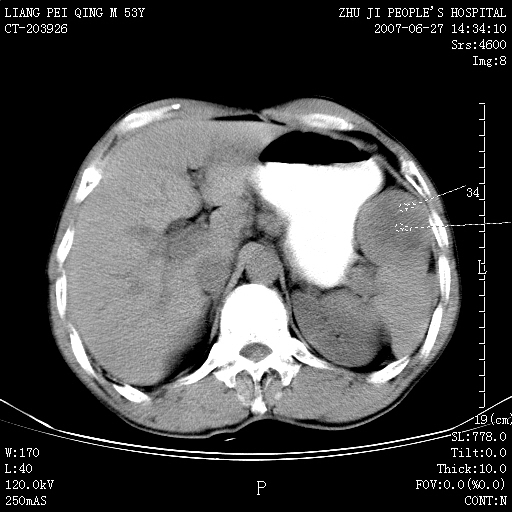

以下是引用余辉在2007-6-27 18:46:00的发言:[br]病灶多发,内可见大片状低密度区,病灶病灶等密度区轻度强化,动脉期后期病灶低密度区与高密度区对度增加,考虑1淋巴瘤2转移瘤3血管内皮细胞瘤(不知有否静脉期及延迟期扫描)

以下是引用zzzzhhhhaaaannnn在2007-6-27 20:44:00的发言:[br]脾脏 肋骨转移可能性大,下腔静脉内有癌栓

以下是引用狙击手在2007-6-28 10:35:00的发言:[br]1:定位:来源于脾脏。2:强化:强化,但不均匀。3:下腔静脉癌栓?下腔静脉充填不均匀与增强时间有关,延时即可明确。4:肋骨破坏?看起来并不确切。综上考虑几个最常见诊断:1;淋巴管瘤;2;血管内皮肉瘤(高度恶性,早期即可转移,常见肝,肺,骨)3;转移瘤(无特征性,只有肝或其它腹腔脏器有类似病变时,才可提示之)